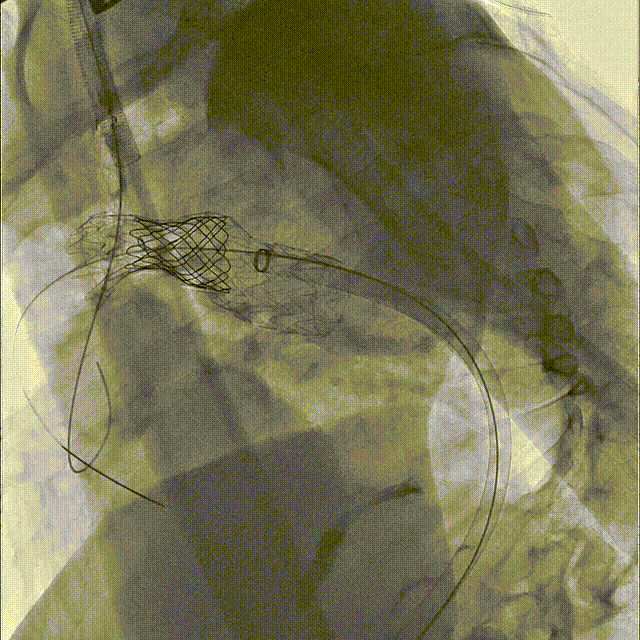

第四步、经左颈总动脉穿刺针破膜原位开窗,球囊逐步扩大窗口,确保左颈总动脉血供。考虑还需要植入CP支架,先在左颈总留置导丝并不植入小支架。

第五步、 通过Gore 大鞘内导入NUMED CVRDCP8Z39球扩支架,定位于主动脉弓部缩窄部位释放。然后在左颈总动脉植入Fluency 12*40,球囊后扩。

第六步、结扎左锁骨下动脉近心端,采用Gore-Tex 6mm人工血管行左颈总动脉-左锁骨下动脉旁路移植,左椎动脉近端结扎,远端端侧吻合于左颈总动脉。

第七步、最终造影,关闭手术切口。